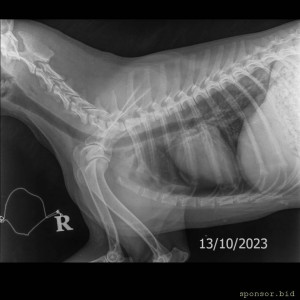

На втором снимке видно как раздроблена кость

Мою собаку сбила машина - IMG_20231013_183654.jpg